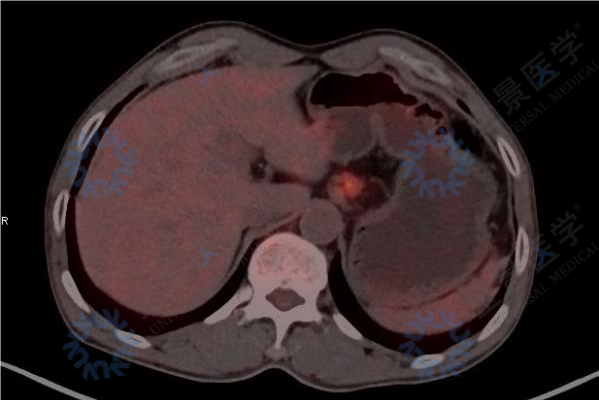

检查结果显示:胸上段食管癌,伴双侧锁骨区、肺门、纵隔及肝胃间隙淋巴结转移。

在王先生的 PET/CT 图像上,医生不仅能看到胸上段食管的高代谢原发肿瘤,更重要的是,在双侧锁骨区、肺门、纵隔、肝胃间隙等多个区域也发现了异常增高的代谢信号。这明确提示这些淋巴结存在转移。这一发现将他的病情准确划分为「伴有远处转移的晚期(IV 期)」 。这种精准分期是选择正确治疗方案的根本依据。